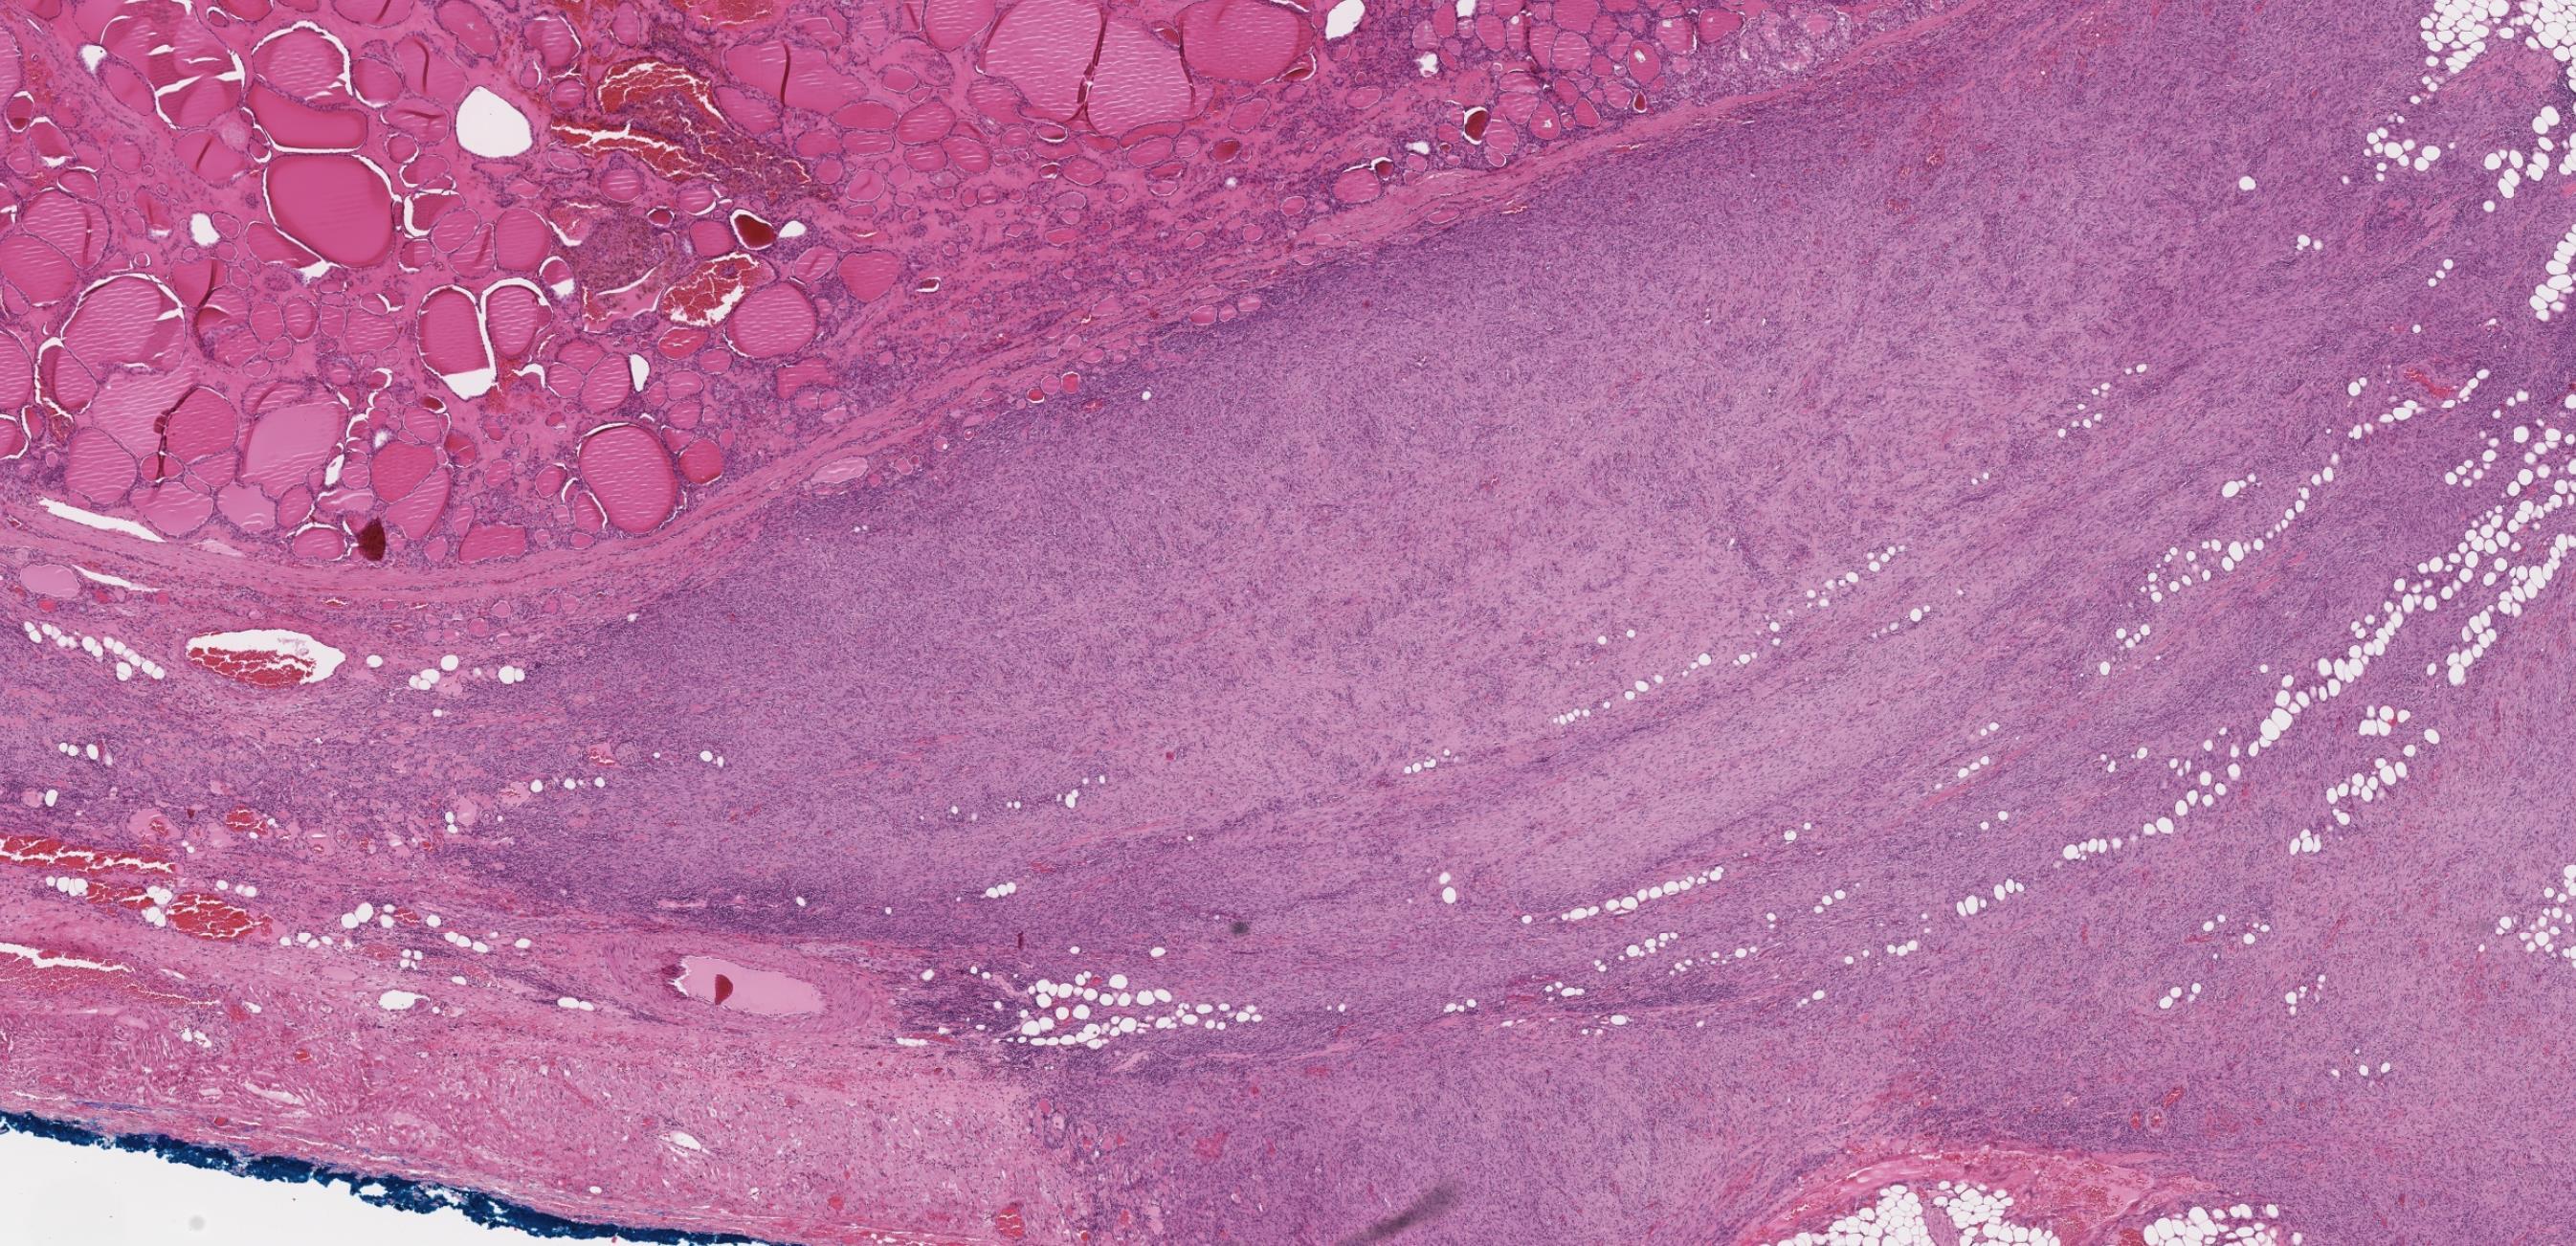

Case 6

32-year-old Female, Right thyroid lobectomy.

Case 6 Diagnosis

Consistent with parathyroid carcinoma

Discussion Differential diagnoses • Parathyroid adenoma with post-biopsy reactive changes • Secondary/tertiary parathyroid hyperplasia with high proliferative activity, fibrosis • Atypical parathyroid tumour • Parathyromatosis • Sporadic • HPT-JT syndrome • Familial isolated hyperparathyroidism • Most cases CDC73 mutations (CDC73 encodes for parafibromin)

Parathyromatosis ?? • Parathyroid tissue growth around site of a former surgery due to implantation of lesional parathyroid tissue • Sometimes indistinguishable from parathyroid carcinoma Atypical parathyroid tumours • Coagulative tumour necrosis, atypical mitotic figure, or loss of parafibromin may represent parathyroid carcinomas. • Perform parafibromin immunohistochemistry -parafibromin deficient atypical parathyroid tumours have an increased risk of recurrence or metachronous disease in other glands, and would warrant long term follow-up